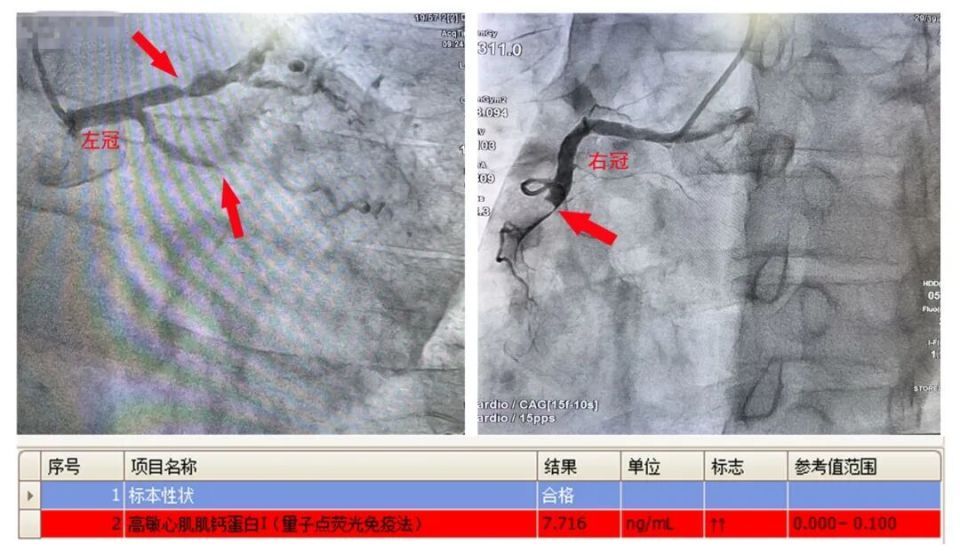

造影检查结果让在场的医护人员都倒吸了一口凉气:江先生心脏上的三支主要血管,有两支已经完全堵死,剩下一支也堵了大半,就像三条给心脏供血的“主干道”,两条彻底断流、一条严重拥堵,心脏随时可能因为“缺氧缺粮”停止跳动。

“导丝准备!”胸痛中心副主任晏彪冷静下令。尽管江先生血压波动频繁、操作难度极大,但团队每一步都精准到位。9时27分,导丝成功穿过堵塞血管、恢复血流——从救护车到院至血管开通,仅用28分钟,远低于国家胸痛中心90分钟的达标线,创下了鄞州二院胸痛中心急救的“新速度”。